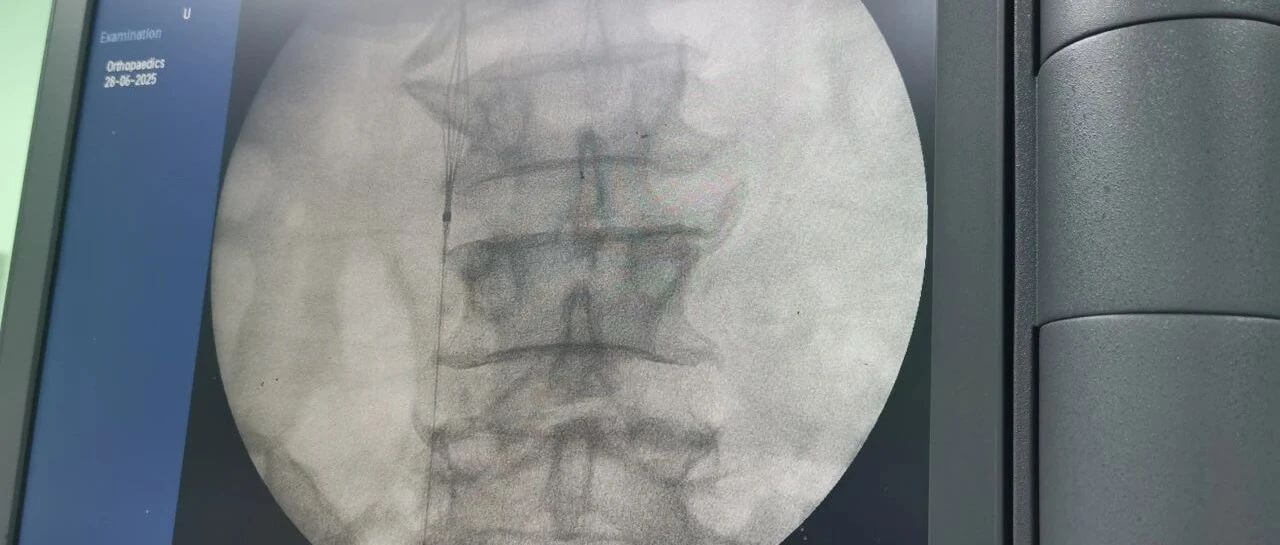

面對這一嚴(yán)峻挑戰(zhàn),羅軍副院長團(tuán)隊(duì)果斷決策,先行實(shí)施“下腔靜脈濾器植入術(shù)”。手術(shù)團(tuán)隊(duì)?wèi){借精湛的技術(shù),在患者的下腔靜脈(人體最大的靜脈干)內(nèi)精準(zhǔn)放置了一個特殊的“濾網(wǎng)”裝置——腔靜脈濾器。它的核心作用就是充當(dāng)“血栓攔截網(wǎng)”:

攔截脫落的血栓:有效捕捉從下肢深靜脈脫落的血栓碎片,防止其隨血流進(jìn)入心臟和肺部。

預(yù)防致命肺栓塞:從根本上大幅降低患者在骨折手術(shù)期間及術(shù)后康復(fù)階段發(fā)生肺栓塞的風(fēng)險。

保障后續(xù)手術(shù)安全:為接下來必須進(jìn)行的、耗時較長的骨盆髖臼粉碎性骨折修復(fù)手術(shù)(尤其是利用3D打印技術(shù)進(jìn)行的精準(zhǔn)手術(shù))掃除了最大的安全隱患,提供了至關(guān)重要的手術(shù)安全保障期。